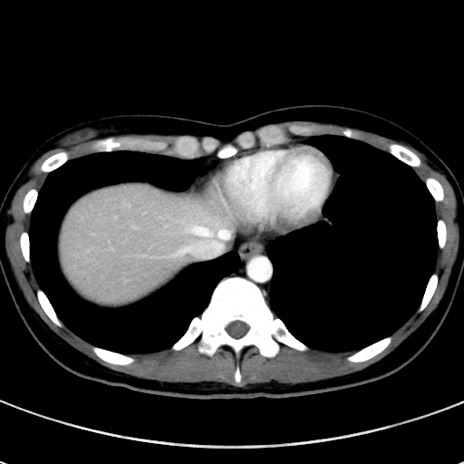

症例17(横断像)

【症例】20歳代女性

【主訴】嘔吐、下腹部痛

【現病歴】昨日夕食後に嘔吐し下腹部痛が出現。本日になっても嘔吐持続し改善しないため来院。

【身体所見】意識清明、BT 37.2℃、BP 108/67mmHg、腹部:平坦、やや硬、下腹部正中から右にかけて圧痛あり、反跳痛軽度あり、tapping pain(+)。

【データ】WBC 13600、CRP 14.94